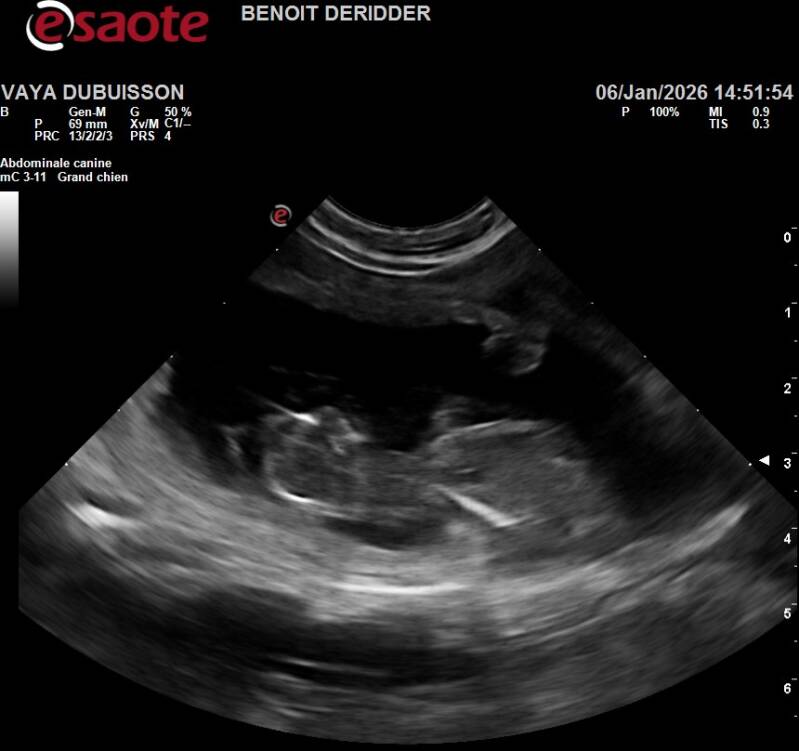

Ce 06/01/2026, je suis allée chez le veto pour une échographie afin de confirmer la gestation de Vayana mais à coup sûr, j'en étais convaincue parce que Vasco & Vayana c'est magique, je dirai même plus une alchimie, ils ne leur suffit qu'un seul accouplement pour que la magie opère..

Ça y est, Benoît commence à passer sur le ventre de Vayana et nous pouvons apercevoir sur l'écran jouxtant en hauteur de la table quelque chose ou ressemble à ... Oui oui dit-il avec un sourire joviale, Vayana a remis ça, on en compte approximativement 7 mais connaissant la demoiselle, nous ne serions pas surpris d'en avoir 10...